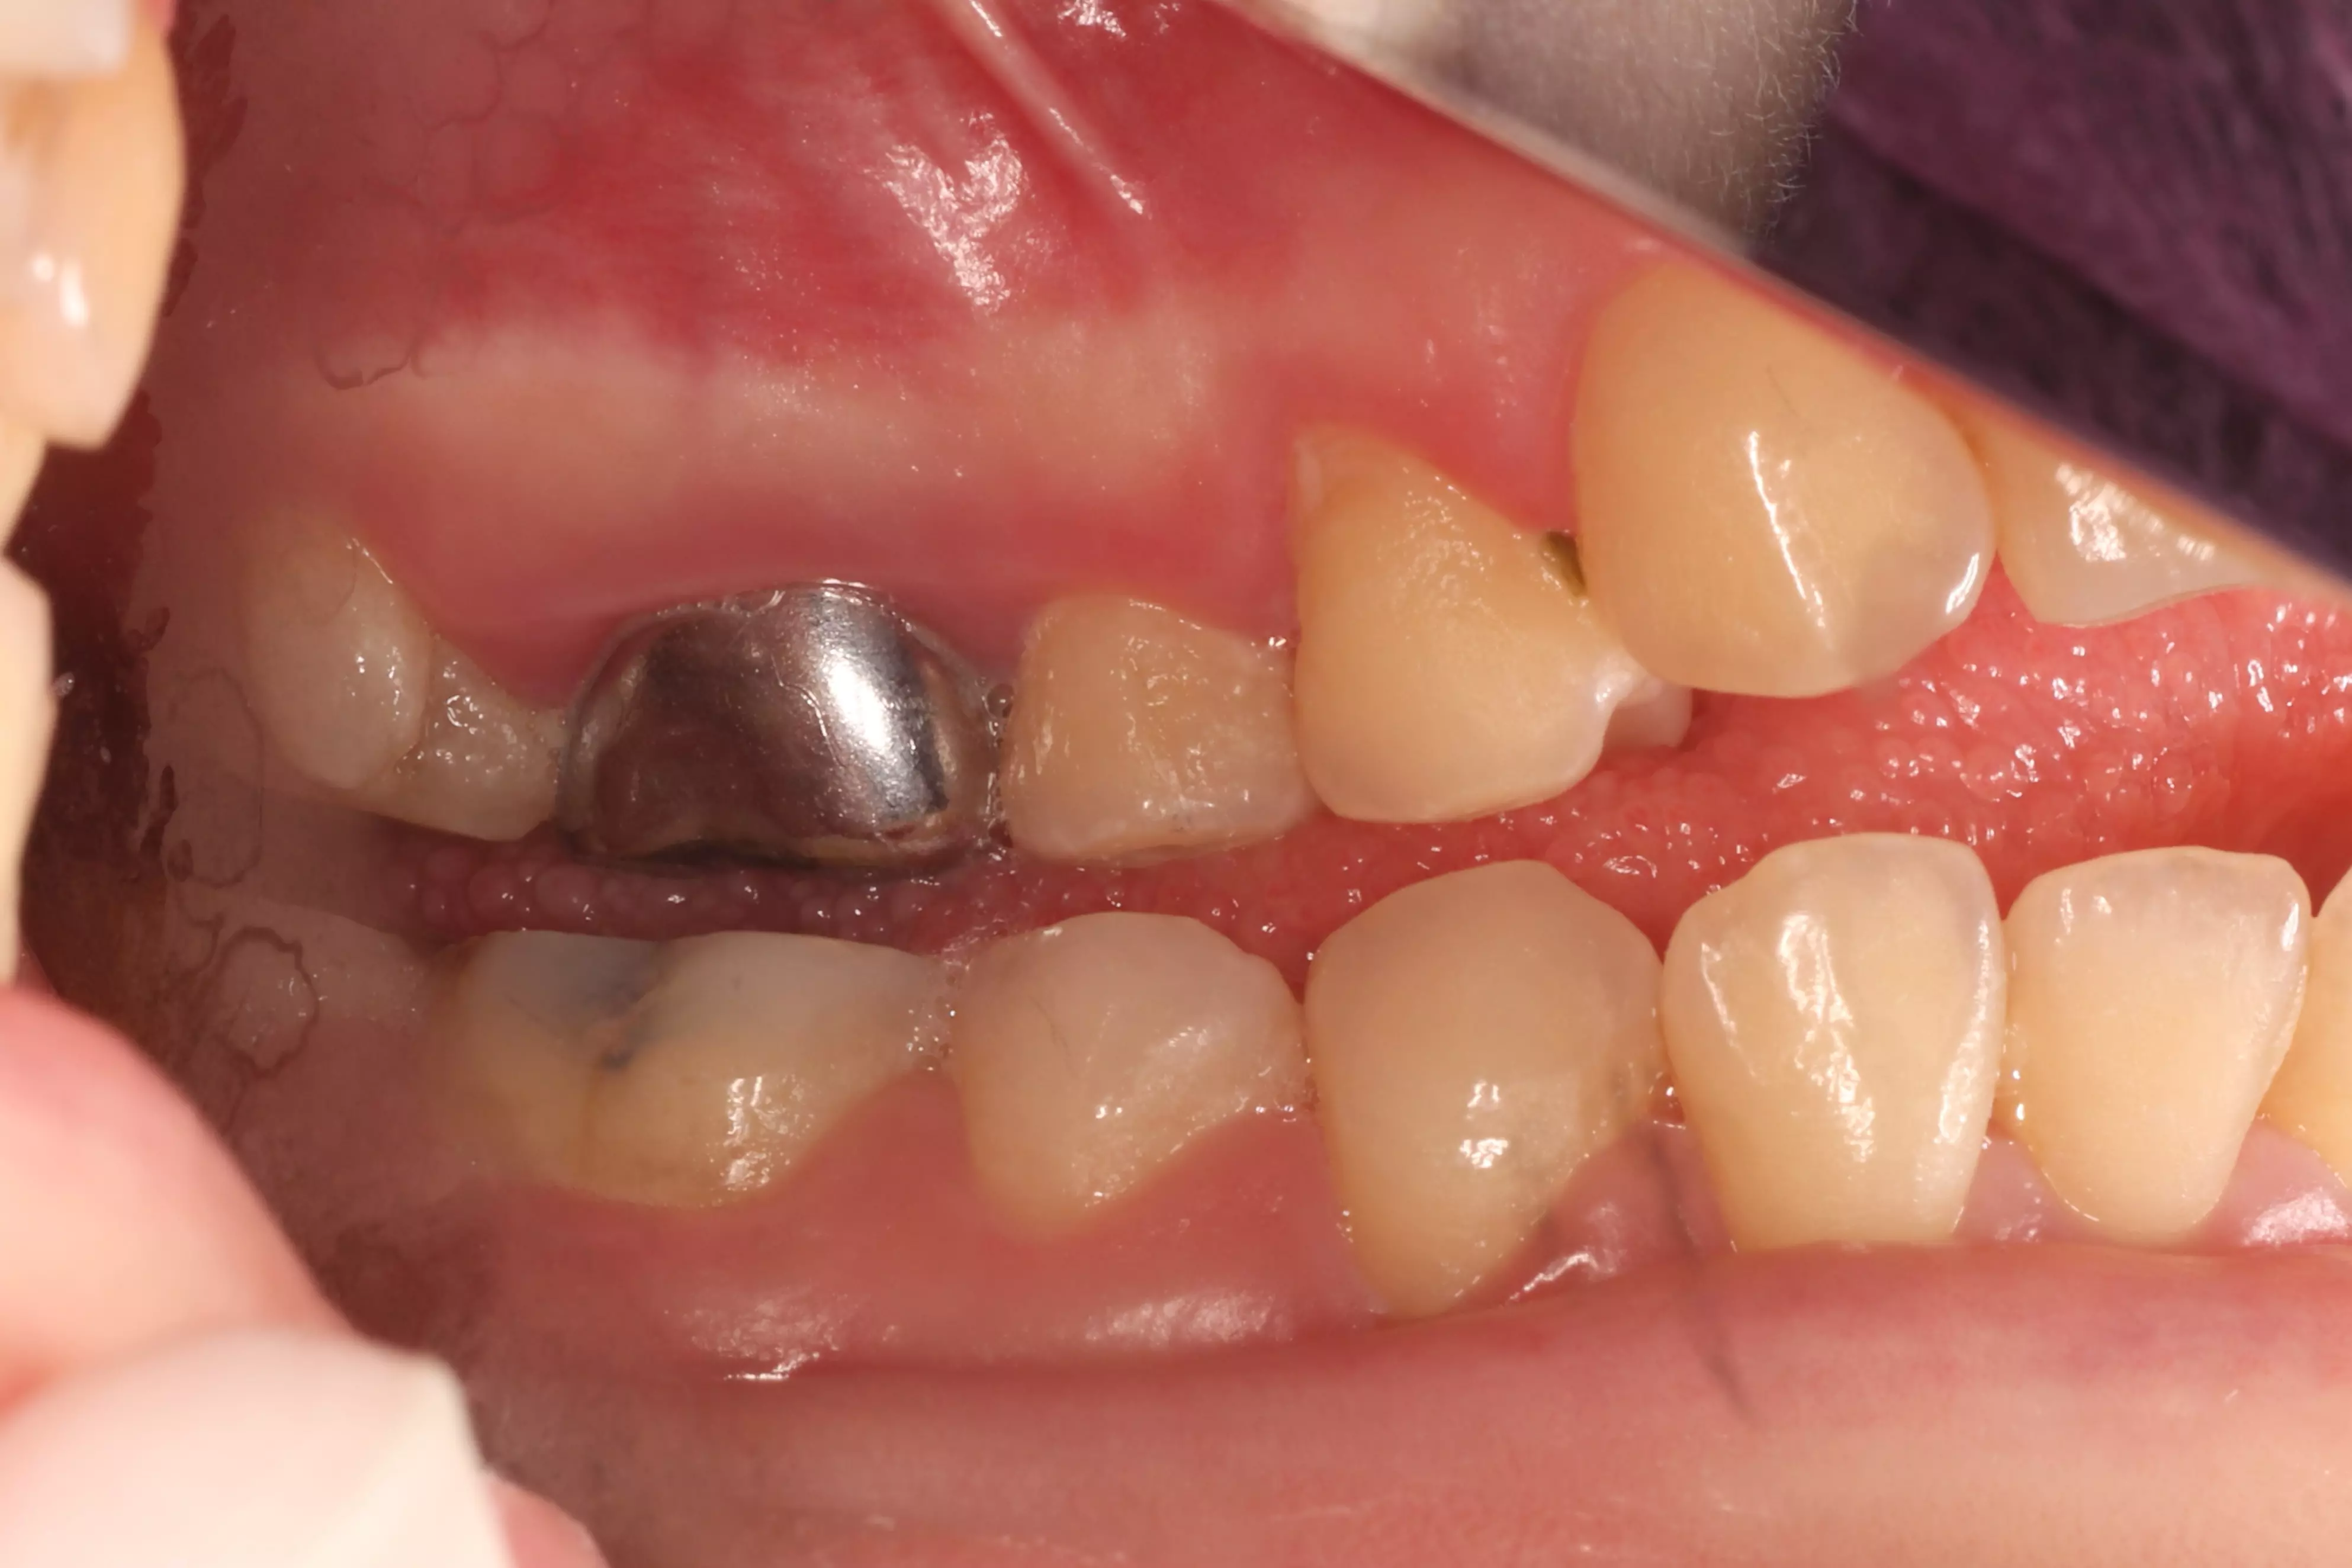

下方是患者初診的照片。患者有嚴重的咬合不正,但是基於身體條件,不適合進行齒顎矯正。下顎左側的缺牙使得她原本就不好的咬合功能變得雪上加霜,吃東西變得更困難。

下方是治療完成的照片。歷時四個多月,在患者、家屬、及醫療團隊的共同努力下,終於完成新的假牙製作。